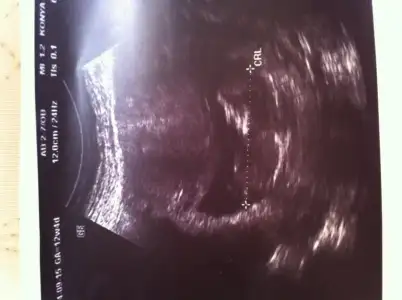

cnm burda kac haftalik sayet 12 ve uzeri ise ctrl cizgisinin altinda bir cikinti goruyorum

paralel gibi ama eminde degilim cunki hemen ustunde bi cikinti daha var net degil yani

Orkdm canım resim kağıdını elime aldım baktım ctrl çizgisinin altındaki sırta çok yakın gibi geldi o nub olabilir miki acaba,neyse artık bi sonraki kontrolde öğreniriz inşaallah,Saol ilgilendiğin için:)